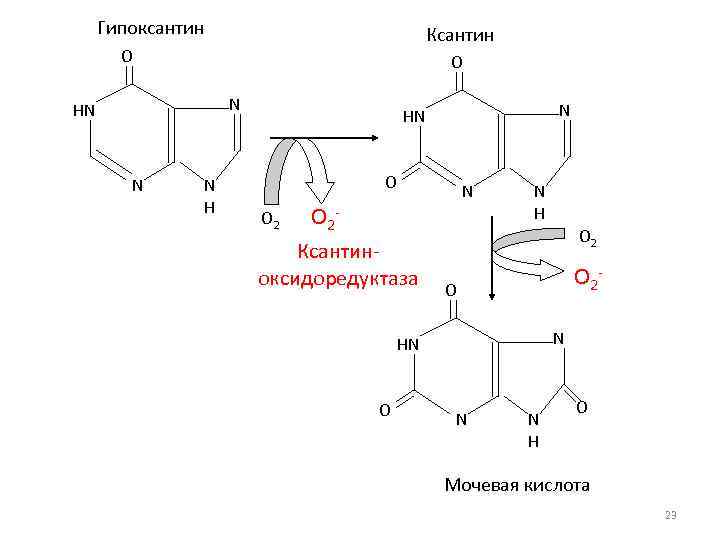

Образование оксида азота в макрофагах Аргинин Mg, Zn Вит. А Синтазы оксида азота Ксантиноксидоредуктаза Гипоксантин Ксантин Инозин Mo, Cu, Fe Вит. В 2 NO ONOO-

Гипоксантин Ксантин O O N HN N N HN O O 2 N O 2 - Ксантиноксидоредуктаза N H O 2 - O N HN O N N H O Мочевая кислота 23

Активаторы ксантиноксидоредуктазы • Рибоксин (инозин) • Молибден • Медь • Железо • Рибофлавин-5 -фосфат 25

Молибден В организме человека массой около 70 кг содержится примерно 9, 3 мг молибдена, что составляет 0. 00001% массы тела. Наибольшая его концентрация характерна для печени и тонкой кишки. Тем не менее, у человека молибден АБСОЛЮТНО необходим для функционирования трёх ферментов: ксантиноксидазы (ксантин-оксидоредуктазы), альдегидоксидазы и сульфитоксидазы. 26